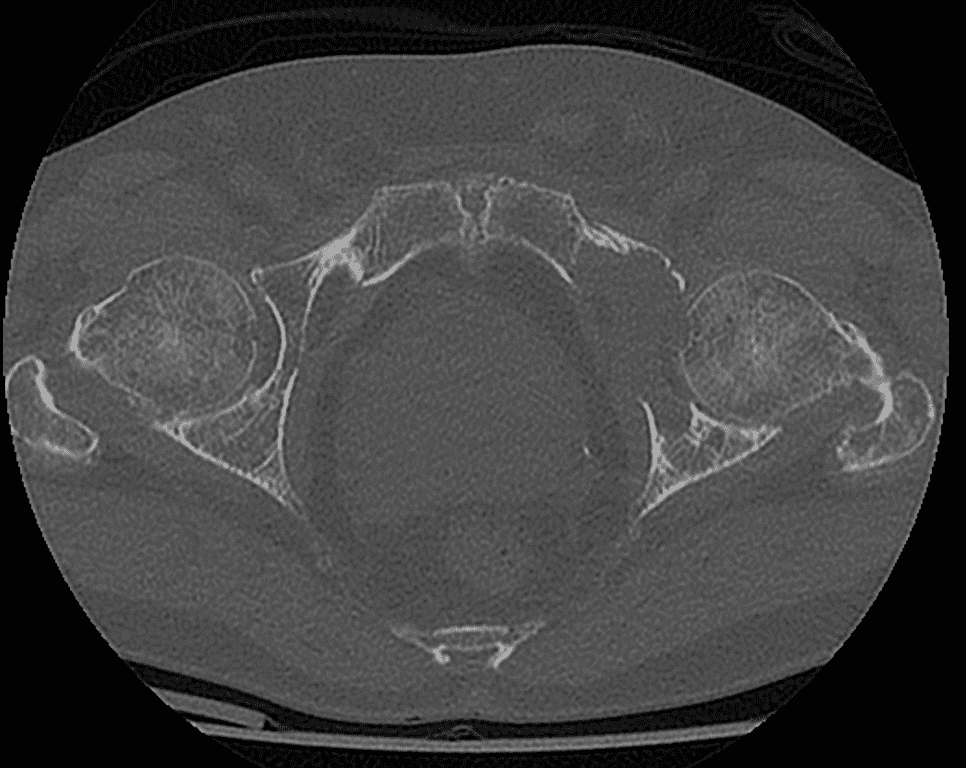

Analyse des images CT pour définir la trajectoire optimale du vissage en fonction du schéma de fracture.

Déterminer des repères anatomiques et la configuration osseuse pour minimiser le risque de pénétration intra-articulaire.